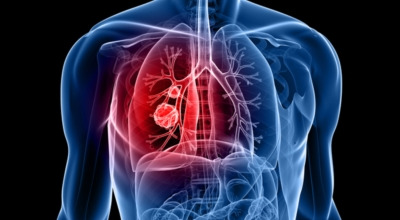

폐암 초기 증상 중 하나로 가슴 통증이 있습니다. 폐암 환자의 약 3분의 1 정도가 흉통을 호소하는데요, 이는 폐 가장자리 부분에 종양이 생기고, 그 종양이 암세포를 생성하며 흉벽과 흉막에 닿아 통증을 유발하기 때문입니다.

흉통은 여러 원인으로 발생할 수 있지만, 폐암에서 기인한 흉통은 지속적으로 쿡쿡 찌르는 듯한 느낌과 함께 가벼운 통증이 아닌 둔탁한 통증이 동반되는 경우가 많으니 주의가 필요합니다.